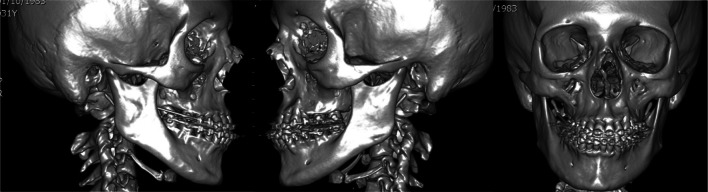

32-year-old male who underwent 2 surgeries. The first was a MAZLFIIIO with a 6 mm advancement through a coronal and transconjunctival approach. The second surgery was a Le Fort I osteotomy with a 5 mm advancement and a 6 mm advancement genioplasty. The midface deficiency is shown in the CT scan (Fig. 17). After the MAZLFIIIO, a CT scan was made, where the symmetric osteotomies have an advancement of 6 mm and an upward movement of the right side, of 3 mm. Only 2 L-shaped plates were placed over the zygomatic bones, and orbital meshes were also used to cover the 6 mm gap at the floor of the orbit (Fig. 18).

Fig. 17.

Preop CT scans

Fig. 18.

CT scan after the first surgery, where the symmetry of the osteotomies is demonstrated as well as the L-shaped plates on both zygomatic bones with 2 orbital meshes covering the orbital floor gap. On the frontal view, symmetry is observed in osteotomies and in the plates. The orbital meshes are used to cover the 6 mm gap at the floor of the orbit and firmly adapted to the inner orbit